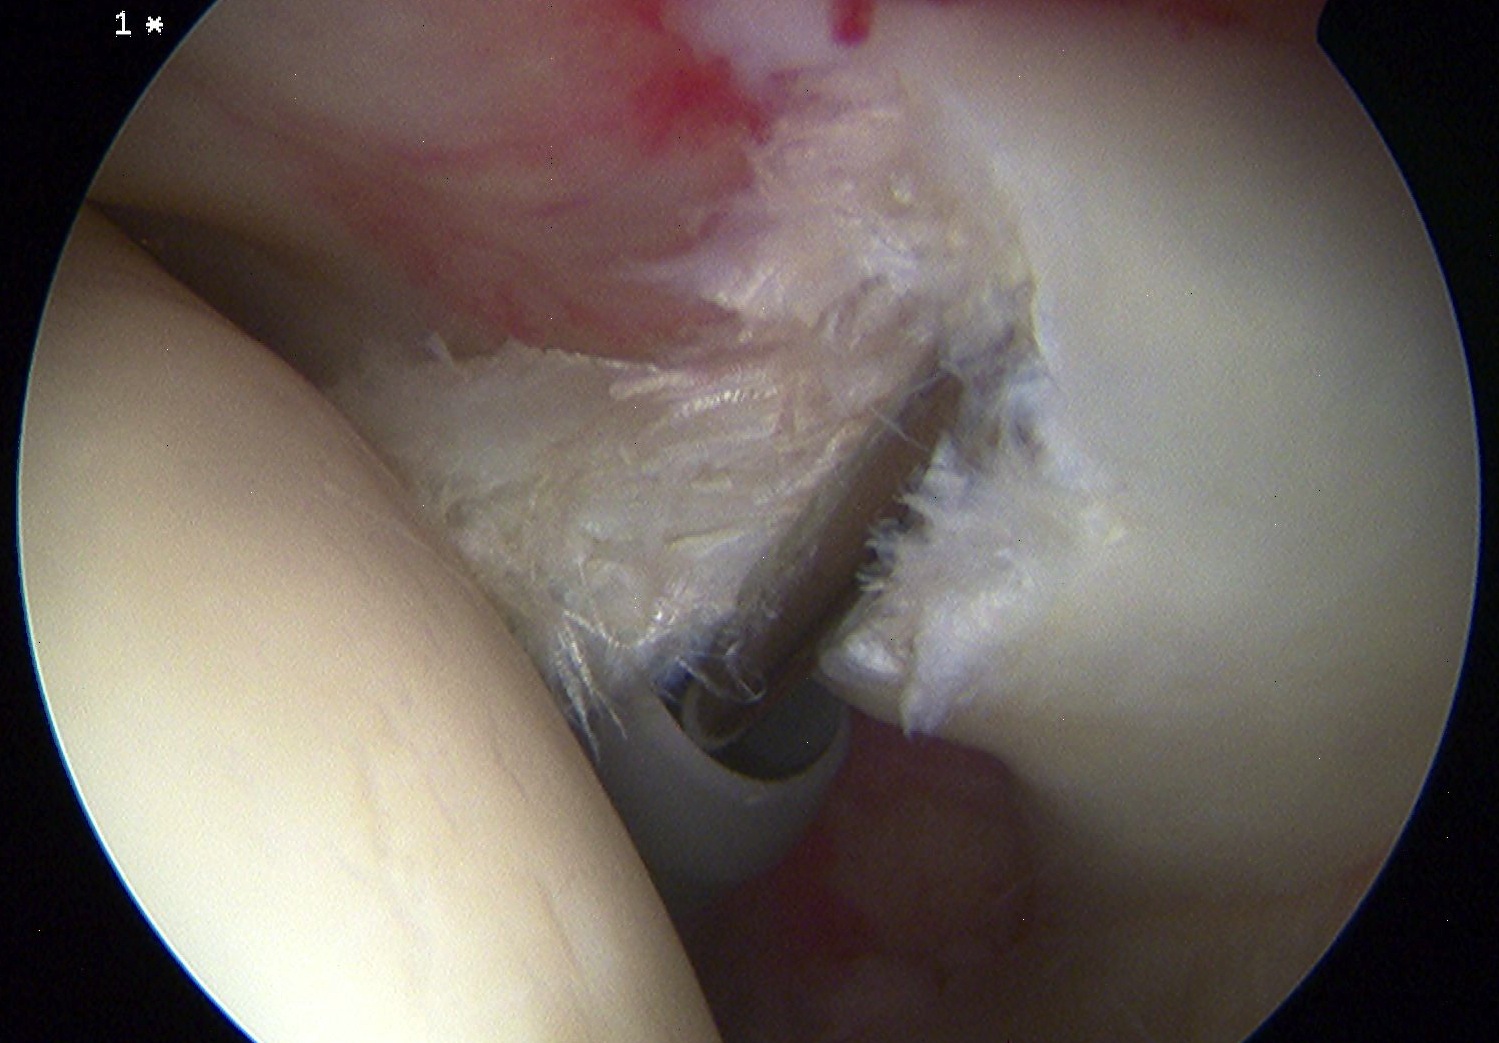

Arthroscopy

Tendonopathy

Medial subluxation of LHB

Arthroscopic suprapectoral biceps tenodesis

- tag biceps tendon with high strength suture and release

- repair superior labrum with one or two anchors

Tag biceps and release